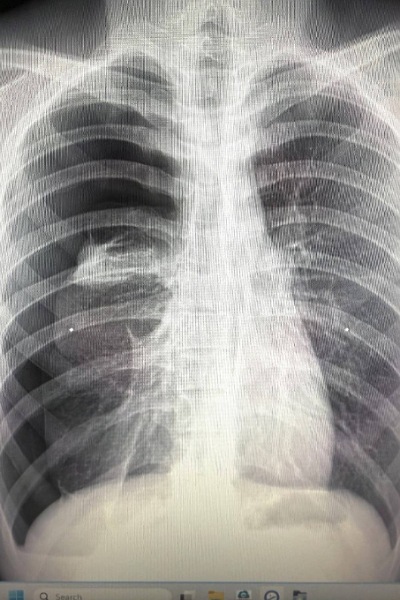

รศ.นพ.ศิระ เลาหทัย แพทย์ผู้เชี่ยวชาญศัลยศาสตร์ ทรวงอกเฉพาะทางด้านการผ่าตัดส่องกล้องในช่องทรวงอก โรงพยาบาลวชิรพยาบาล กล่าวว่าจากการวินิจฉัย ส่วนมากการทำ X-Ray หรือ ทำเอกซเรย์คอมพิวเตอร์ (CT Chest) หรือ MRI อาจพบได้ แต่อย่างไรก็ตามยังไม่มีการตรวจใดมีประสิทธิภาพที่สามารถวินิจฉัยโรคนี้ได้โดยตรง โดยในบางรายอาจพบถุงลมบริเวณยอดของปอดร่วมด้วยได้ (Lung Bleb) ในส่วนของการรักษาในโรคลมรั่วในเยื่อหุ้มปอดนี้ ประกอบด้วย 2 อย่าง ได้แก่1)การรักษาด้วยการผ่าตัด(ส่องกล้อง) และ2)การรักษาด้วยยา